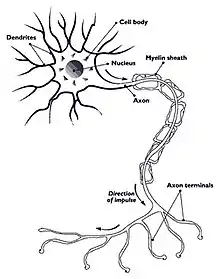

| Nerve with myelin sheath | |

Hereditary neuropathy with liability to pressure palsy (HNPP) is a peripheral neuropathy, a condition that affects the nerves.[4] Pressure on the nerves can cause tingling sensations, numbness, pain, weakness, muscle atrophy and even paralysis of the affected area. In normal individuals, these symptoms disappear quickly, but in sufferers of HNPP even a short period of pressure can cause the symptoms to occur. Palsies can last from minutes or days to weeks or even months.[4][1]

HNPP is caused by a mutation in the gene PMP22, which makes peripheral myelin protein 22. This protein has a role in the maintenance of the myelin sheath that insulates nerves, resulting in insufficient conductivity in the nerves. HNPP is part of the group of hereditary motor and sensory neuropathy (HMSN) disorders and is linked to Charcot–Marie–Tooth disease (CMT).[5]

The condition is caused by a mutation in one copy of the gene PMP22 (peripheral myelin protein 22, located at locus 17p11.2). This makes it autosomal dominant.[8] PMP22 is involved in maintaining the myelin sheath that surrounds nerves to facilitate conductivity.[5] The mutation causes haploinsufficiency, where the activity of the normal gene is insufficient to compensate for the loss of function of the other gene.[9]

The peripheral myelin protein 22 gene encodes a 22-kD protein that comprises 2 to 5% of peripheral nervous system myelin.[10]